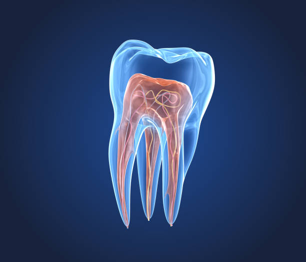

Root Canal Therapy